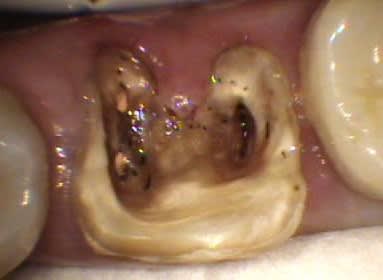

Voici un cas moins gentil avec élimination de la cause du problème pour reprendre les termes de Marc.

Il s'agit d'une patiente de 90 ans sur qui je reconstituais les secteurs postérieurs mandibulaires, ce qui fera l'objet d'un prochain post d'ailleurs, et dont un simple détartrage révélait la présence d'une énorme carie sous le pilier distal d'un bridge reliant la 23 à la 26.

Ayant intérêt à éviter de commencer un gros chantier alors qu'un autre était en cours, j'ai opté pour dégager et éliminer cette carie en conservant provisoirement ce bridge qui tenait bien, avant de traiter ce secteur en tachant de récupérer la racine de la 26 si possible.

J'ai déjà récupéré de nombreuses racines à ce stade et les ai utilisées comme piliers de bridges ou les ai couronnées, dans la mesure ou l'ancrage alvéolaire était solide et en respectant les furcations pour y assurer l'hygiène.

La gencive lasérisée devient très ferme avec le temps et le déchaussement se stabilise. Ces restaurations se comportent bien sur un recul de plusieurs années.

Un exemple: une 46 avec furcation linguale dénudée après lasérisation et restauration par une endocouronne céromère réalisée il y a 9 ans et sans signe clinique avec une excellente attache gingivale malgré la perte osseuse, les 3 avant dernières images ont été prises lors d'un contrôle en mars dernier ...

9 années pour cette patiente de 90 ans, cela vaut bien le coup d'essayer vous ne croyez-pas? (dernière radio)

Avec le laser, on devient bien plus conservateur...